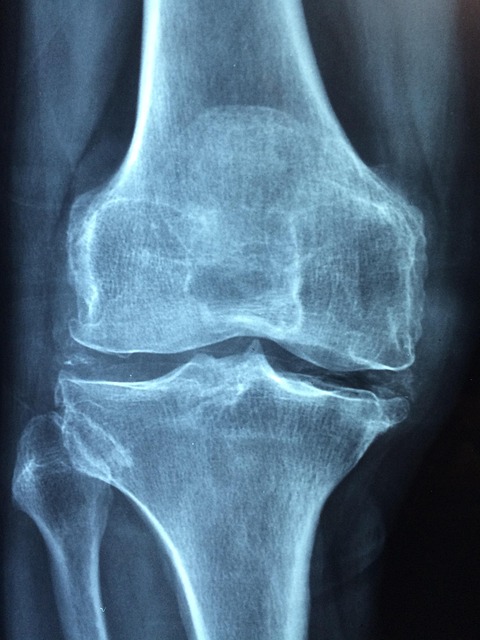

골다공증이 무서운 이유는 '골절' 때문이다. 뼈가 약해지면 길을 걷다 살짝 미끄러지거나, 심지어 재채기 같은 사소한 충격에도 뼈가 으스러질 수 있다. 주로 손목, 척추(허리), 대퇴골(고관절) 부위에서 골절이 잘 일어난다. 특히 노년층의 '고관절(엉덩이뼈) 골절'은 치명적이다. 뼈가 부러지면 꼼짝없이 누워 지내야 하는데, 이 과정에서 욕창, 폐렴, 혈전증 등 합병증이 발생하여 1년 내 사망률이 20%에 달한다는 통계도 있다. 또한, 척추 뼈가 서서히 찌그러지면서 키가 줄어들거나 등이 굽는 현상(꼬부랑 할머니)이 나타나기도 한다.